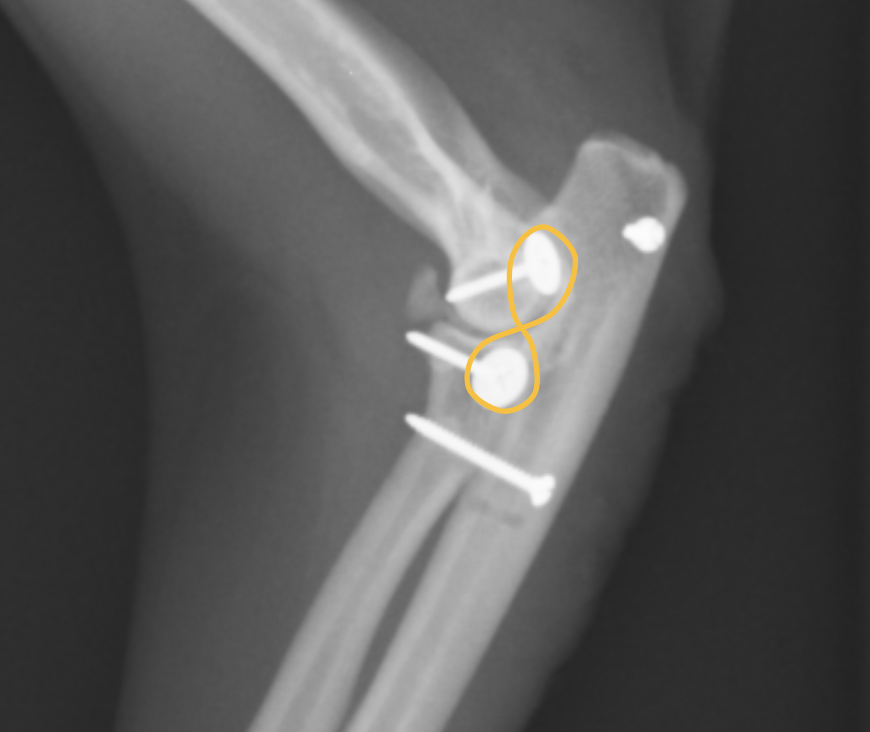

こちらが患肢の横から見たX線です。紫が上腕骨で、オレンジが橈骨、緑が尺骨です。このX線だと、上腕骨と橈尺骨が離れているのが分かると思います。橈骨と尺骨の脱臼はよくわかりません。

手術ではまず輪状靭帯の再建を行いますが、靭帯を縫合してもすぐに断裂してしまうことから、尺骨から橈骨に向けて一本のスクリューを打ちます。この方法で尺骨と橈骨を固定します。固定すると、腕を捻る方向は動かなくなるため、猫の場合、猫座りやよじ登るときにねじるような動きはやりにくくなります。

この黄色の矢印のスクリューが尺骨と橈骨を固定しています。